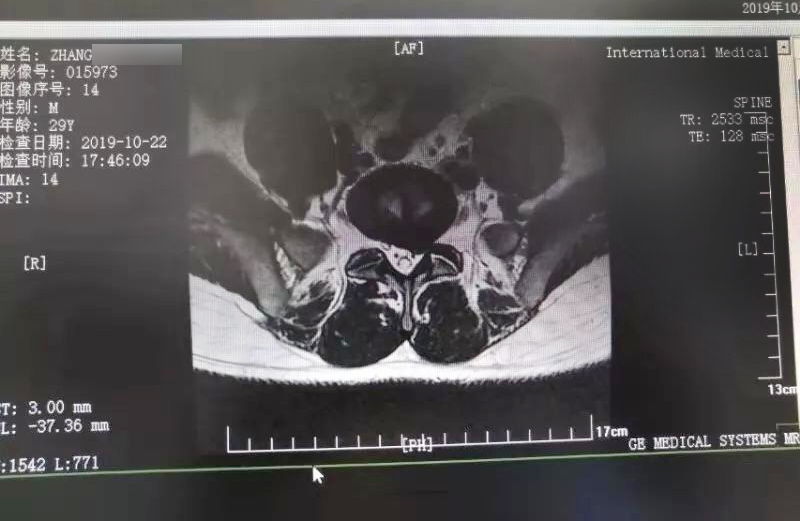

三秦網(wǎng)報(bào)道—西安國際醫(yī)學(xué)中心骨科醫(yī)院成功完成首例椎間孔鏡手術(shù)

三秦網(wǎng)報(bào)道—西安國際醫(yī)學(xué)中心骨科醫(yī)院成功完成首例椎間孔鏡手術(shù)。點(diǎn)擊閱讀。